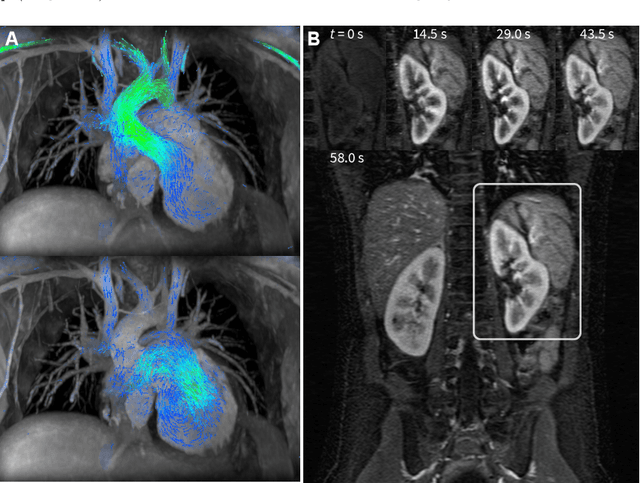

Abstract:Compressed sensing in MRI enables high subsampling factors while maintaining diagnostic image quality. This technique enables shortened scan durations and/or improved image resolution. Further, compressed sensing can increase the diagnostic information and value from each scan performed. Overall, compressed sensing has significant clinical impact in improving the diagnostic quality and patient experience for imaging exams. However, a number of challenges exist when moving compressed sensing from research to the clinic. These challenges include hand-crafted image priors, sensitive tuning parameters, and long reconstruction times. Data-driven learning provides a solution to address these challenges. As a result, compressed sensing can have greater clinical impact. In this tutorial, we will review the compressed sensing formulation and outline steps needed to transform this formulation to a deep learning framework. Supplementary open source code in python will be used to demonstrate this approach with open databases. Further, we will discuss considerations in applying data-driven compressed sensing in the clinical setting.